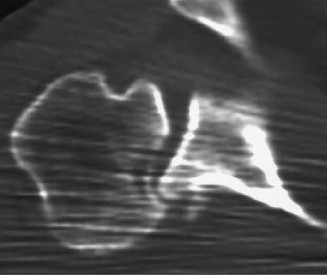

Identify the muscles that compose the force couples in the transverse and coronal planes? CASE 3 A 35-year-old male has had left shoulder pain for 4 months, ever since a low-speed motor vehicle accident (MVA). Physical examination demonstrates preserved range of motion but pain and some weakness with Jobe’s testing. His imaging is shown in Figure 2–8.

Figure 2–8_Reproduced with permission from Stadnick ME. _Partial Rotator Cuff Tears. MRI Web Clinic. 2007 (Apr).

What is the most likely diagnosis?

The correct answer is (A). These are best diagnosed on an MRI as seen in the imaging provided; addition of intra-articular contrast can further improve this study. Answer B, full-thickness rotator cuff tear, is incorrect as the bursal side of the tendon can be seen to be in continuity. Answer C, a SLAP lesion, will be visualized as a labral tear on a coronal MRI and will be found at the biceps root. Answer D, an ALPSA lesion, will be most clearly seen on an axial MRI. It is a variant of a Bankart lesion where the labrum is displaced medially and inferiorly rolling down the glenoid neck underneath the periosteum.

MRI remains the most popular imaging modality for diagnosing rotator cuff tears. Normal rotator cuff tendon appears dark on both T1 and T2 sequences. Tears may be noted as being full-thickness, articular-sided, bursal-sided, or intrasubstance. They are visualized as a disruption in the regular contour of the tendon and increased signal intensity on T2 sequences. Occasionally, an MR arthrogram may provide additional information regarding a cuff tear, although this is not routinely ordered.